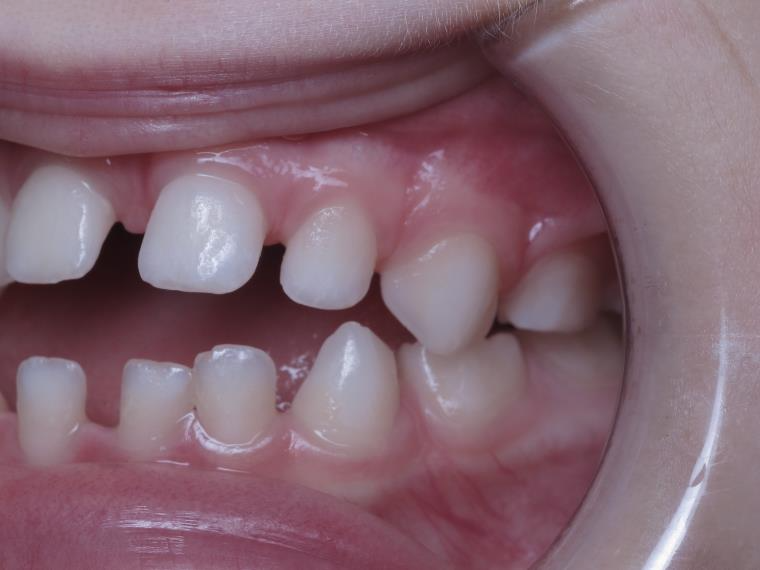

18 béance inversé droit 4 ans

inversion des dents postérieur et espace entre l'arcade du haut et du bas (béance)

bilan de début et en cours de traitement